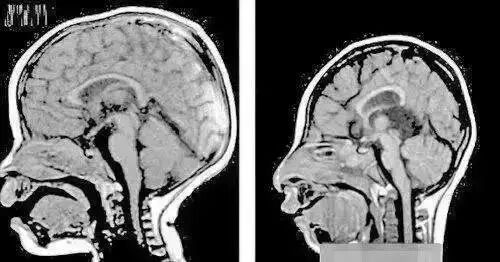

小头症

这种病毒的可怕之处是,可能是新生儿罹患小头症的罪魁祸首。该病毒会干扰胎儿神经系统发育,导致胎儿流产、新生儿小头畸形甚至死亡

患小头症的婴儿,容易大脑发育不良,出现身体残疾和智力障碍,比如视听障碍、行动障碍和认知障碍。